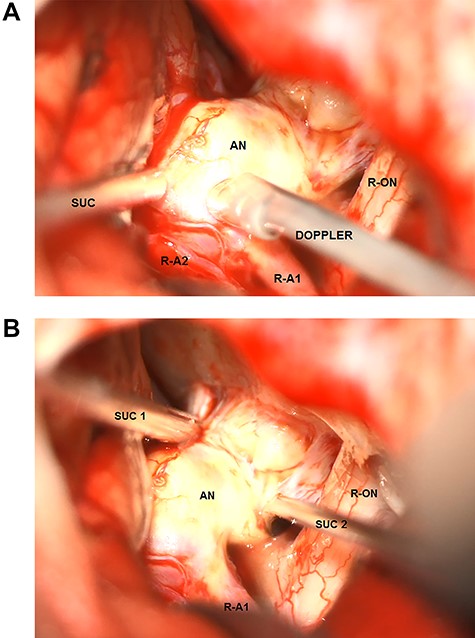

Under general anesthesia, a six French guiding catheter (Envoy, Codman Neuro, Raynham and USA) was positioned in the cervical segment of the right internal carotid artery. A Prowler Select 21 micro catheter (Cordis, Santa Clara and USA) was navigated into the aneurysm followed by the uncomplicated implantation of an HPC-coated pCONus2 bifurcation stent (phenox, Bochum and Germany; Fig. 4A). The petals of the device covered the wide neck of the aneurysm, enabling the complete occlusion of the aneurysm with coils (Fig. 4B). Final control showed complete occlusion of the aneurysm as well as patent perfusion of both anterior cerebral arteries (Fig. 4C). No embolic events were observed. Clinical outcome was excellent according to the glasgow outcome scale 5 and modified ranking scale 0. The patient was discharged and kept on dual antiplatelets (Clopidogrel and Aspirin) for 6 months and single antiplatelet (aspirin) thereafter for another 6 months.

The pCONus2 device for the treatment of a calcified aneurysm of the Acom. (A) Digital subtraction angiography showing the placement of the pCONus2 bifurcation stent with its petals being located at the level of the aneurysm neck and the proximal stent ending at the distal segment of the internal carotid artery. (B) The implantation of several coils with a second micro_catheter navigated through the already opened pCONus. (C) Postprocedural digital subtraction angiography showing the completely occluded aneurysm with preservation of the Acom.

Wide-necked bifurcation aneurysms continue to present a challenge for interventionalists [7]. pCONus devices (Fig. 4) first introduced in 2014 for wide-necked bifurcation aneurysms-are novel devices using the ‘waffle-cone’ technique [8]. These implants are intra-saccular devices that do not affect blood flow because of a stent body structure with an articulated crown of pedals, which are gently pressed against the vessel wall. The pCONus2 device has additional pedals for improved coverage of the aneurysm neck and a shorter shaft to decrease coil prolapses into the parent vessel [9].

In their meta-analysis, Sorenson et al. found a technical success rate of 100% and a technical complication rate of 0% for pCONus devices. Perioperative morbidity and mortality rates were also low (7 and 0%, respectively; [10]).

Because of the aneurysm morphology, we decided to use the pCONus2-assisted coil device. Consequently, complete endovascular occlusion of the aneurysm was successful with excellent outcome.